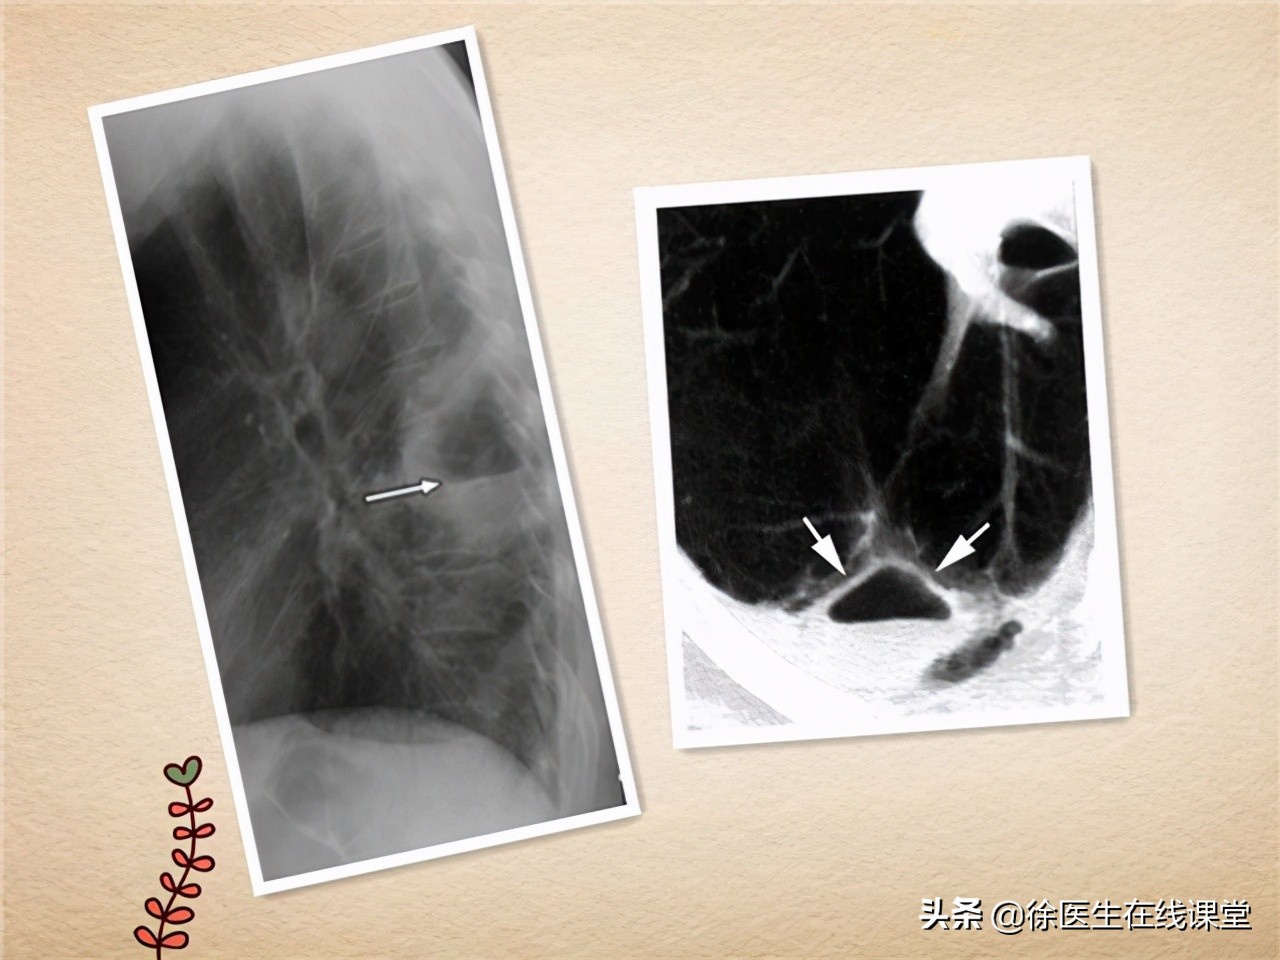

②其次,在第一次CT检查时,发现“肺叶存在炎性病变”,这其实是细菌性肺炎和肺脓肿的共同特征。同时“未出现空洞”,这就很容易使人排除掉肺脓肿,因为肺脓肿有一个非常典型的表现就是 肺部出现空洞或者说是空腔 。然而早期的肺脓肿却往往并没有空洞形成,因此很容易造成误诊。如图所示,便是肺脓肿空洞的典型CT影像(箭头所指示的三角形阴影区域):